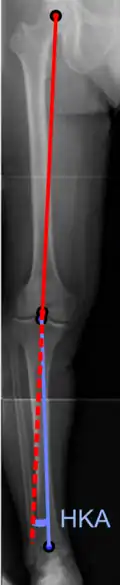

On projectional radiography, the degree of varus or valgus deformity can be quantified by the hip-knee-ankle angle,[7] which is an angle between the femoral mechanical axis and the center of the ankle joint.[8] It is normally between 1.0° and 1.5° of varus in adults.[9] Normal ranges are different in children.[10]

Hip-knee-ankle angle -

Hip-knee-ankle angle by age, with 95% prediction interval[10]